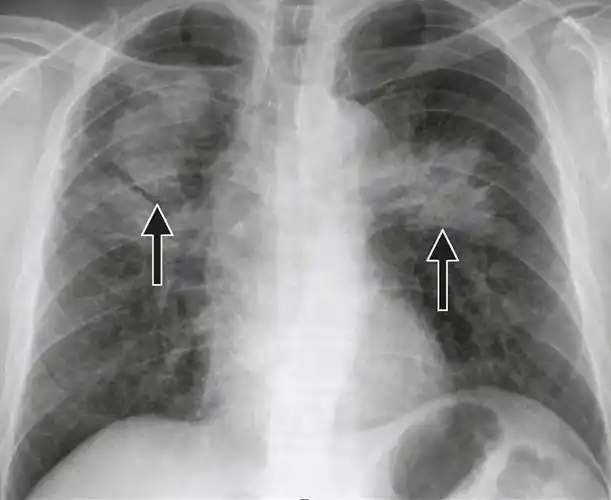

l 二期尘肺,总体密集度二级的小阴影分布范围超过四个肺区,或者三级的